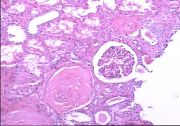

| 2021年12月10日 (五) 13:22 | 24号切片-小叶性肺炎-镜下观1.jpg (文件) |  |

145 KB | Cirno.9 | 基于MsUpload的文件上传 | 1 |